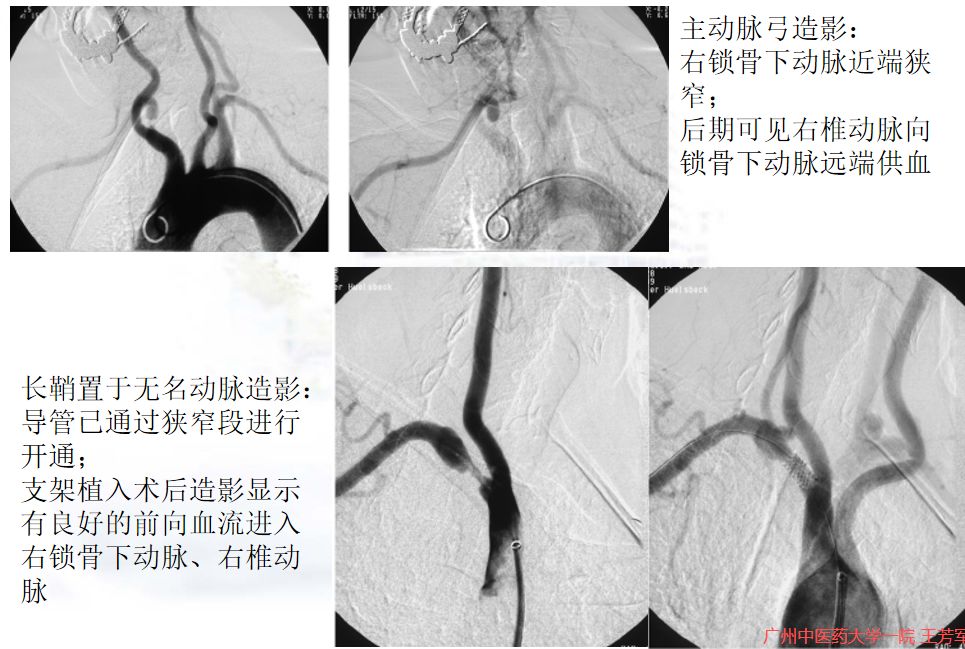

介入治疗过程

一般来说,介入疗效是”立竿见影“的,影像学图像可清晰显示手臂的血流恢复,椎动脉的窃血现象纠正,从逆向血流变为正向血流。患者术后即会觉得手臂”暖暖的“,力量也会大多了,而且感觉会”神清气爽“,似乎智力都上升了!

介入治疗前后DSA图像对比